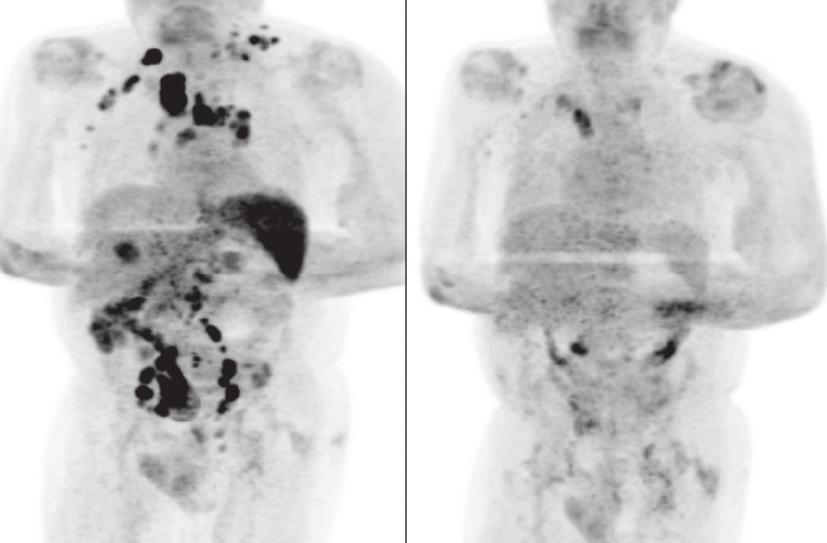

Legenda: Tomografia computadorizada mostra redução do linfoma após paciente ser infectado pelo coronavírus (imagem do lado direito) Foto: Reprodução/Britsh Journal of Haematology

Um homem de 61 anos com linfoma de hodgkin, câncer no sistema linfático, teve remissão da doença após ser infectado pelo novo coronavírus. O caso foi publicado pelo Britsh Journal of Haematology, periódico médico do Reino Unido, em 2 de janeiro.

O homem passou 11 dias internado e recebeu alta para se recuperar em casa. Quatro meses depois, a avaliação médica indicou que o linfoma havia reduzido e exames revelaram resolução generalizada da linfadenopatia.

A quantidade do vírus Epstein-Barr reduziu de 4.800 cópias/mL para 413 cópias/mL.